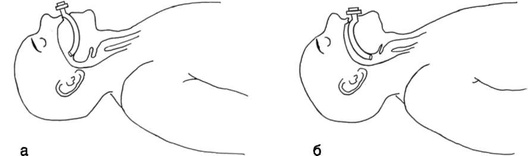

ОРОТРАХЕАЛЬНАЯ ИНТУБАЦИЯ

Шаг 1. Позиционирование головы пациента - разгибательное (классическое джексоновское) или «принюхивающееся» (улучшенное джексоновское) положение (рис. 2.43).

Рис. 2.43. Позиционирование пациента: а - классическое джексоновское; б - улучшенное джексоновское («принюхивающееся»)